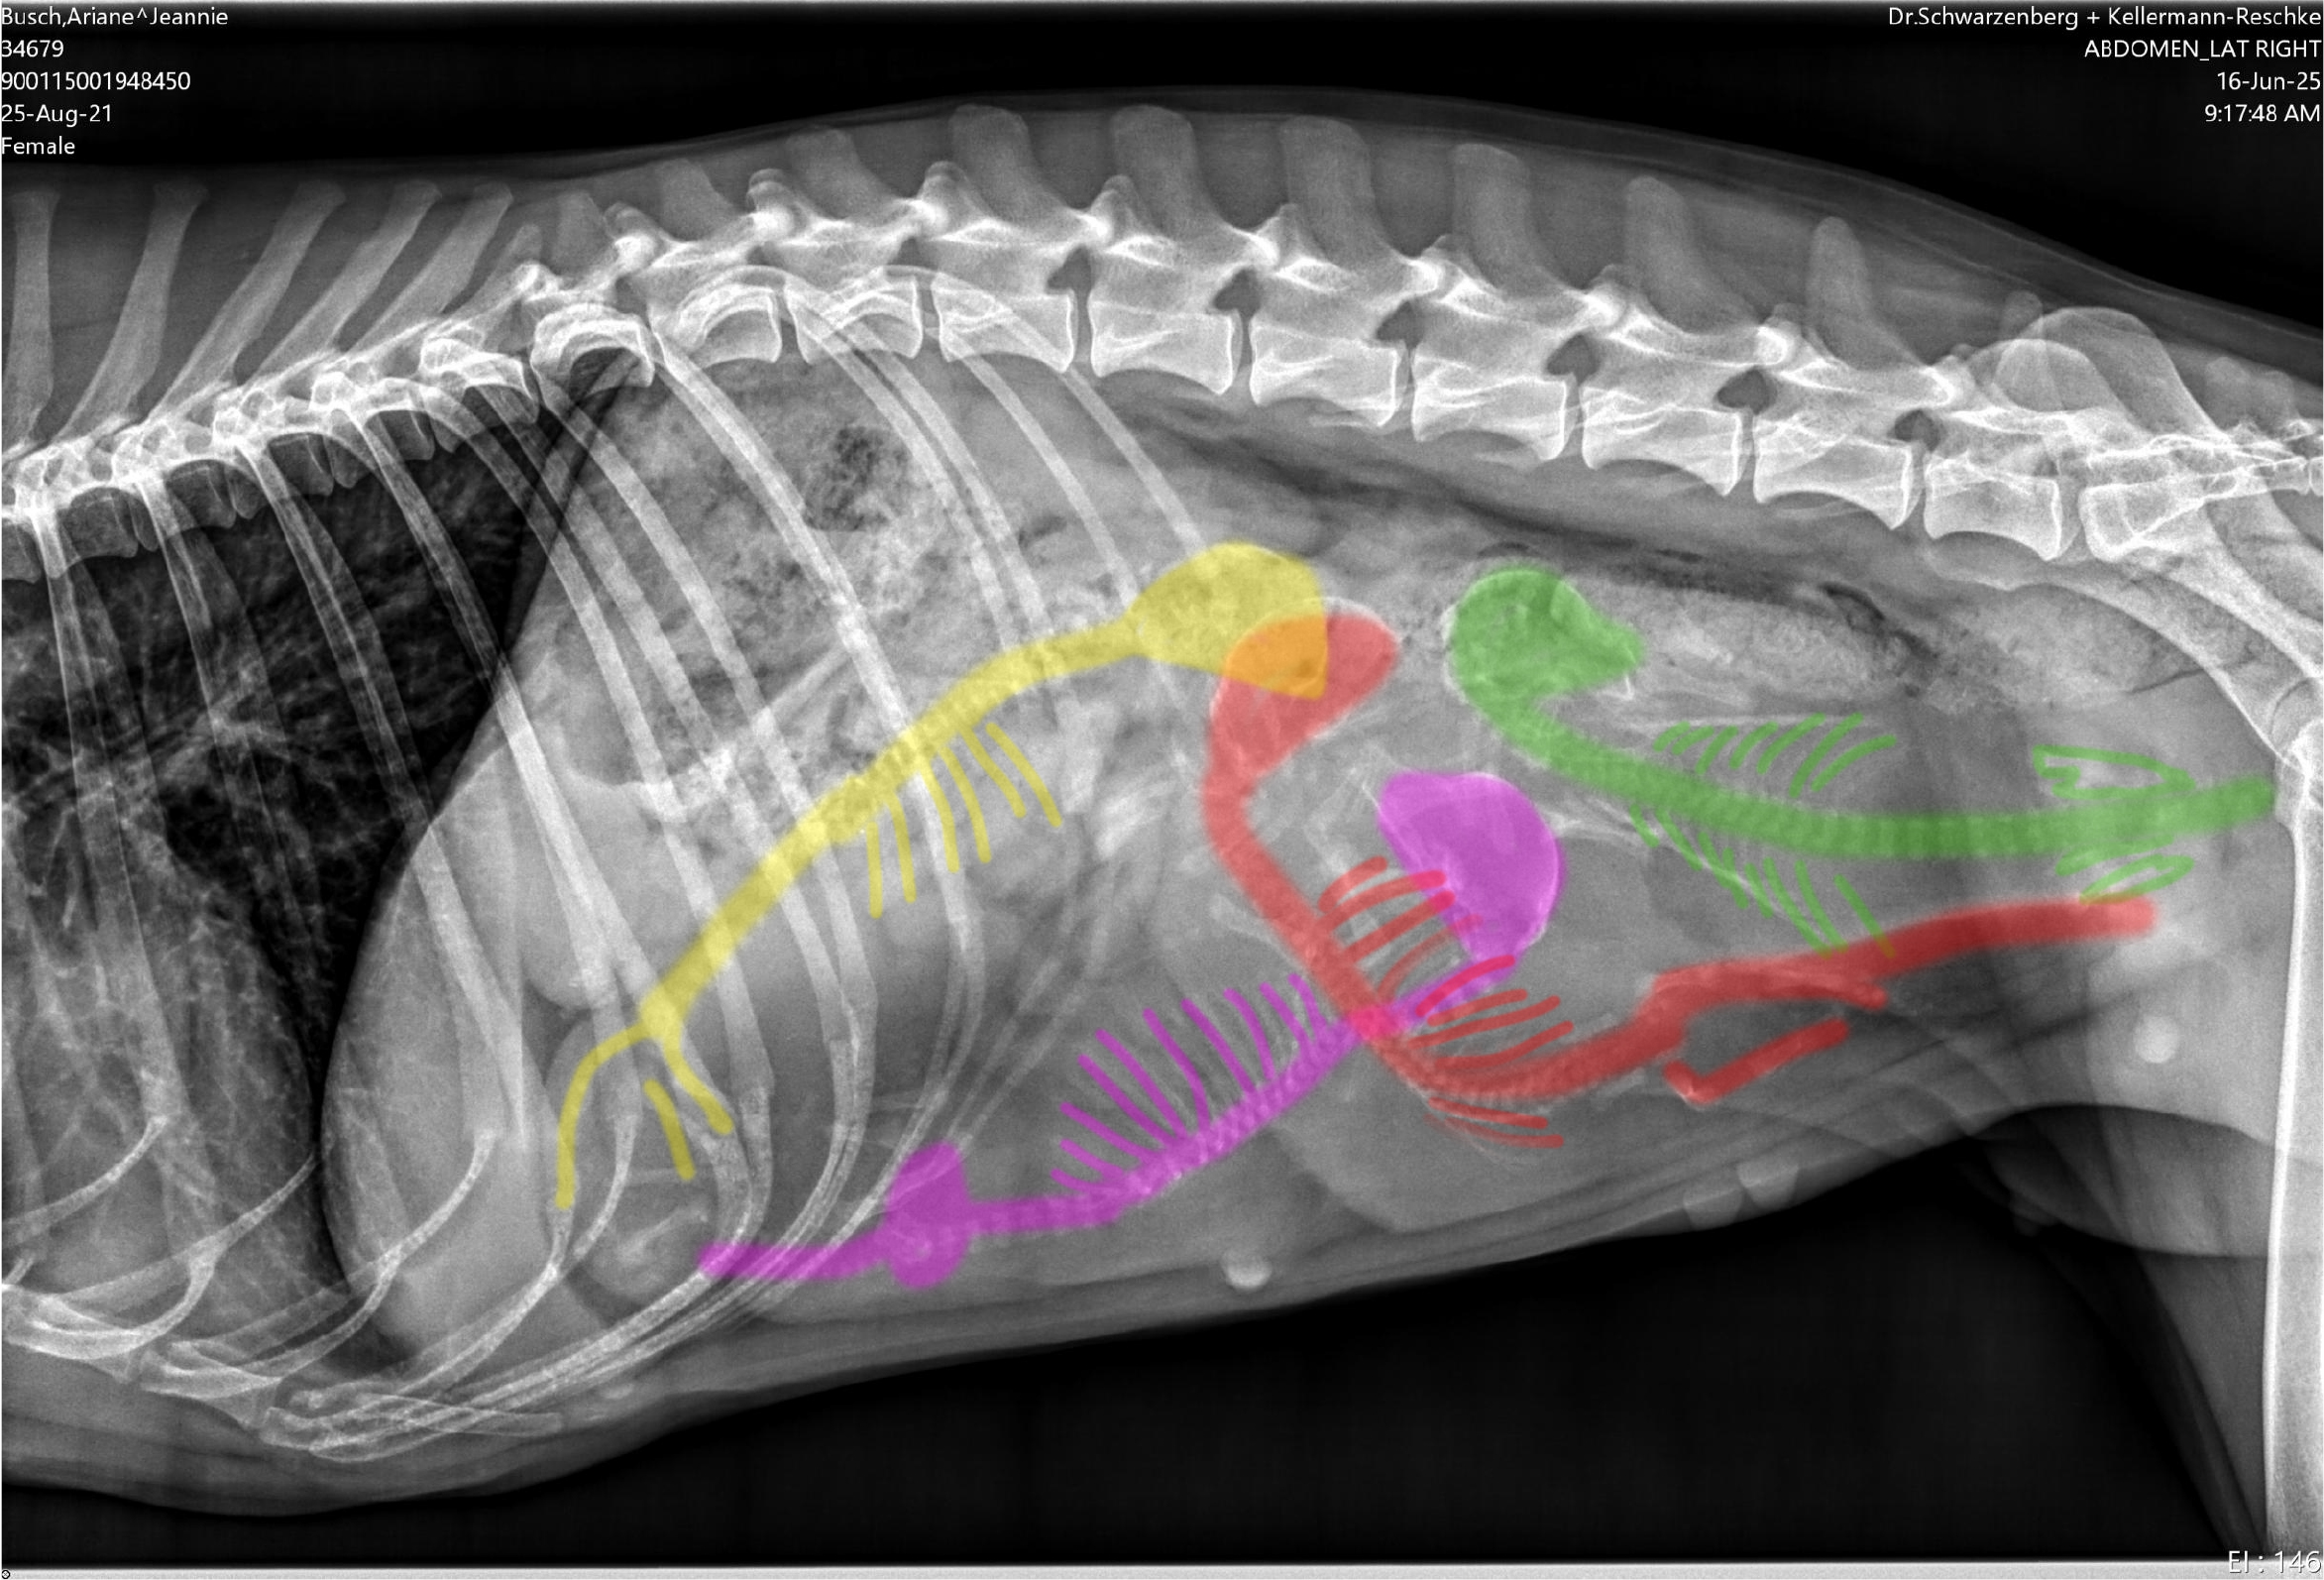

Unsere bezaubernde Jeannie „Tova‘s Riesling Surprise in Germany“ wurde Ende April von unserem charmanten Mio „Golden Nugget's Achilles“ gedeckt.